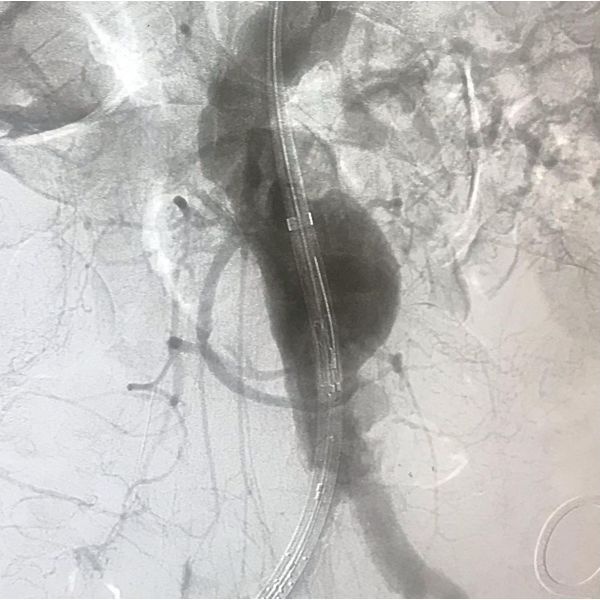

Пациента направили на консультацию с ангиохирургом. Учитывая увеличение диаметра аневризмы и выраженную сопутствующую патологию, мужчине было показано эндоваскулярное протезирование нижнего отдела аорты.

В плановом порядке ему установили стент-графт брюшной аорты.